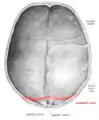

Lambdoid suture seen from above.

The lambdoid suture is between the paired parietal bones and the occipital bone of the skull. It runs from the asterion on each side.

The lambdoid suture is named due to its uppercase lambda-like shape.